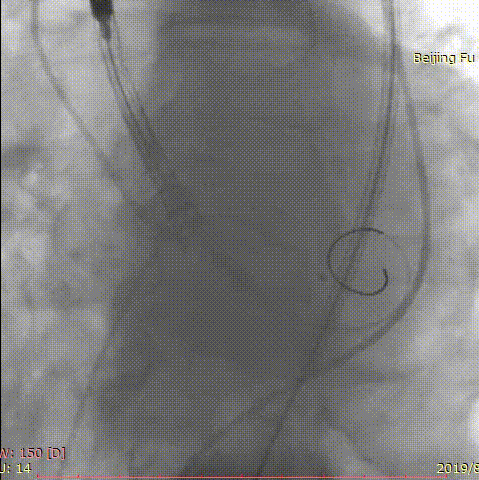

第二位患者是一名84岁男性,因发现心脏瓣膜异常12年,胸闷气短5年入院。曾于我院就诊,超声心动图提示主动脉瓣重度狭窄,2年前行经导管主动脉瓣球囊扩张术,术后患者仍有气短症状反复发作。此次入院后超声心动图提示主动脉瓣球囊扩张术后、主动脉瓣重度狭窄并少量反流,主动脉瓣平均跨瓣压差97mm,收缩期峰值流速6.3m/s,最大压差158.8mmHg。患者高龄、虚弱、消瘦(BMI仅18lg/m2),术前CT评估患者呈带嵴二叶瓣,L-R融合,主动脉瓣环21*29.6mm,周长80.6mm,面积494.7mm2,瓣上多平面测量结果如下。

右侧股动脉为主入路,应用20mm微创心通敖广球囊预扩张,植入24mm微创心通Vifaflow瓣膜,但术中造影提示瓣膜打开不理想,遂应用20*40mm球囊后扩张,术后造影提示无瓣周漏,超声提示主动脉瓣跨瓣压差仅2mmHg。

术前影像